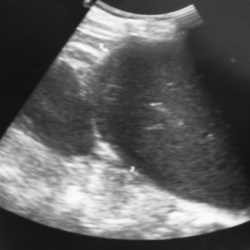

и Два свежих, казалось бы на первый взгляд, похожих случая из сегодняшнего дня.Не могу не поделиться. Какие мнения будут, коллеги, исходя только из картинок УЗИ?Случай № 1...